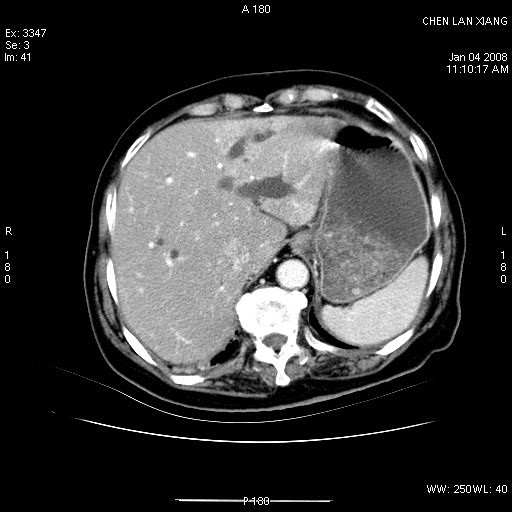

标题: CT11180:女,76岁,腹痛3-4天 [打印本页]

标题: CT11180:女,76岁,腹痛3-4天

女,76岁,腹痛3-4天,b超示:肝内实性肿物,胆囊强回声,胆总管扩张.

考虑:1、胆总管下端结石伴梗阻性肝内外胆管扩张(肝左叶外侧段肝内胆管多发结石、胆管炎);

2、肿囊癌累及肝,不除外 黄色肉芽肿性胆囊炎。

1 胆总管末端结石伴肝内胆管结石,肝内外胆管扩张。2 胆囊扩大,胆囊壁不规则增厚,内见软组织密度影。考虑:慢性胆囊炎,不除外胆囊癌!

标题: 肝右叶病灶

胆囊癌侵犯肝右叶?

1)胆囊癌伴肝脏转移。2)胆总管下端结石、肝内胆管结石伴肝内外胆管扩张。